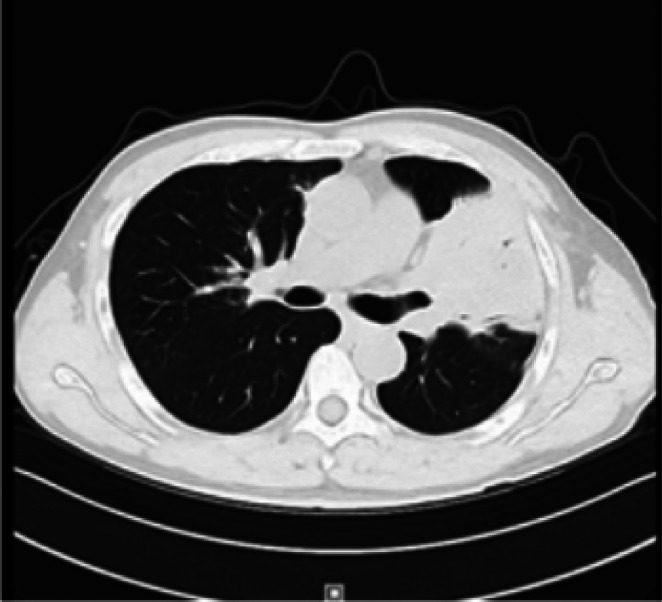

支气管粘膜相关淋巴组织是罕见的粘膜相关淋巴组织(MALT)淋巴瘤的发生部位。由于缺乏明显的临床征象和影像学特征,它经常被误诊和漏诊。在多家三级医院接受肺部感染或肺结核治疗失败后,我们报告了一位男性患者,他的左上肺有一个实性病变长达18年。患者最终在我院采用Jiang技术行CT引导下经皮肺活检(即在常规CT引导的基础上采用激光辅助引导系统)诊断为肺部MALT淋巴瘤。当肺内病变难以用一般肺部疾病来解释时,扩展一个人的视野,综合肺外体征,并努力获得高质量活检标本是至关重要的。

Bronchial mucosa-associated lymphoid tissue is the site of the uncommon malignancy known as mucosa-associated lymphoid tissue (MALT) lymphoma. Due to its lack of distinct clinical signs and imaging characteristics, it is frequently misdiagnosed and underdiagnosed. After receiving unsuccessful treatment for a lung infection or tuberculosis in multiple tertiary care hospitals, we report a male patient who had a solid lesion in his left upper lung for 18 years. The patient was ultimately diagnosed with pulmonary MALT lymphoma at our hospital through a CT-guided percutaneous lung biopsy using the Jiang technique (i.e., employing a laser-assisted guidance system in addition to the conventional CT guidance). It is vital to extend one's perspective, synthesise extrapulmonary signs, and work toward the conditions essential to get a high-quality biopsy specimen when an intrapulmonary lesion is hard to explain by general lung illnesses.